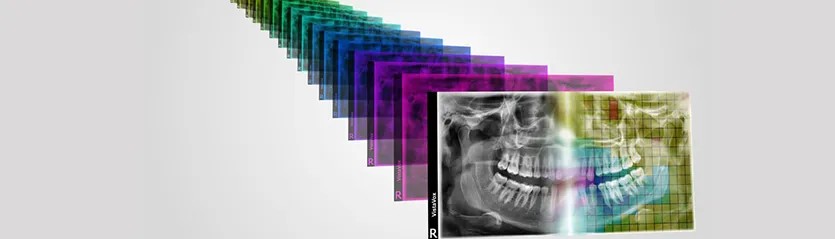

Au sein des cabinets dentaires, le radiographie 3D relève de nombreux défis que la 2D ne permet pas d’assumer. Celle-ci contient plus d’informations que son prédécesseur, tout en facilitant aussi davantage de calculs.

Cette reconstitution numérique s’intéresse à la fois aux dents, aux cartilages et même aux os. Il s’agit d’un examen simple et rapide à mettre en place, très efficace pour poser un diagnostic sûr dans les meilleurs délais.

Pour tirer pleinement profit de la radiographie 3D en implantologie, orthodontie, stomatologie ou encore chirurgie maxillo-faciale, il faut être en mesure de choisir un appareil offrant la meilleure résolution possible, pour une représentation précise des dents et des tissus durs.